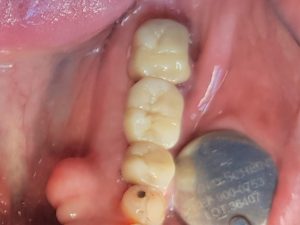

Deze patiënt mist in de linker onderkaak de eerste grote kies. De patiënt wilde graag een vast zittende vervanging voor de ontbrekende kies en daarbij kwam ook, dat hij graag de buurtanden wilde laten kronen. We hebben toen besloten om daar een brug te maken, waarbij er dus kronen worden geplaatst op de kiezen aan weerszijde van de open plek, met tussen de twee kronen een vastzittende ‘zwevende kroon’.

Ik kwam toen met het volgende probleem te zitten: De patiënt had de twee kiezen gedurende zijn leven zo versleten, dat ik bij de kroonomslijping van de achterste kies, zeker met de boor in de zenuw terecht zou komen. Het tweede probleem was, dat als ik de twee kiezen zou omslijpen voor de kronen, de kiezen zodanig verlaagd zouden worden, dat de kronen bij gebrek aan houvast er weer af zouden vallen.

In overleg met de patiënt ben ik vervolgens tot het volgende behandelplan gekomen:

1) Als eerste zou ik een wortelkanaalbehandeling uitvoeren in de achterste grote kies, zodat de zenuw uit de kies verwijderd werd en ik zorgeloos de kies kon omslijpen en verlagen, zonder angst de zenuw te beschadigen.

2) Vervolgens zouden we via een zogeheten ‘flapoperatie’ het kaakbot rond de kiezen enkele millimeters verlagen, zodat er genoeg lengte voor de kiezen werd gecreëerd voor het omslijpen van de kieze: De zogeheten ‘kroonverlengingsprocedure’ (2x).

3) Na het genezen van het kaakbot en het tandvlees rondom de kiezen, zou de brug vervaardigd worden.

Na het verlagen van het bot rondom de twee kiezen, heb ik de wond gehecht met 7 hechtingen van een niet oplosbaar hechtmateriaal .De patiënt kreeg een ‘koelzakje’ om op de wang te drukken tegen eventuele zwelling. De patiënt heeft van ons een extra-soft tandenborstel meegekregen en het advies gedurende 2 weken de twee kiezen slechts voorzichtig te poetsen en het geopereerde tandvlees niet te raken. De patiënt poetst en spoelt gedurende 2 weken met Perio-Aid desinfecterende tandpasta en mondspoelmiddel om ontsteking tegen te gaan. De patiënt heeft een recept meegekregen voor Ibuprofen tegen eventuele later optredende ontsteking en pijn. Ik hield elke dag telefonisch contact met de patiënt om te vragen hoe het genezingsproces verliep en of er pijn of bloeding optrad.

Ik maakte met de patiënt een afspraak om over 3 weken de niet oplosbare hechtingen te verwijderen. Tijdens deze afspraak zag de wond er gezond uit: Het tandvlees was mooi licht roze, niet gezwollen, deed geen pijn en bloede niet. Het tandvlees had zich ook weer sterk aan het onderliggende kaakbot gehecht.

Anderhalve maand later zou het onderliggende kaakbot genoeg zijn genezen en stabiel genoeg zijn om een duurzame brug te vervaardigen van element 35 tot element 37.